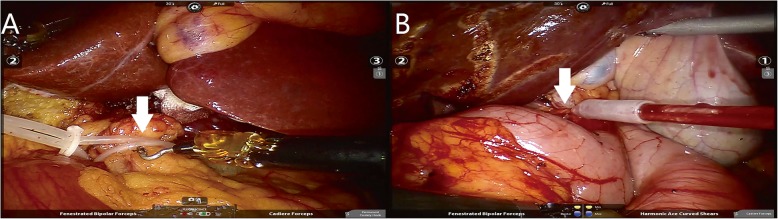

Fig. 4.

Modified Pringle manoeuvre. a, b Hepatoduodenal ligament was encircled and ready to be occluded by the catheter (8F) or rope: hepatoduodenal ligament (A and B, arrow)